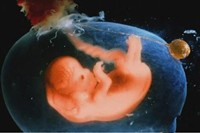

胎兒五個(gè)月時(shí)性器官已經(jīng)發(fā)育完善,你有沒有好奇懷孕五個(gè)月男胎兒長(zhǎng)什么樣呢?如果你對(duì)此感興趣,不如一起來看看懷孕五個(gè)月男胎兒圖長(zhǎng)啥樣...

懷孕六個(gè)月男胎兒圖什么樣?相信這是所有孕媽都感興趣的話題吧。懷孕進(jìn)入六個(gè)月后,此時(shí)孕媽會(huì)越來越感覺得到胎兒的存在,大多數(shù)的孕媽這個(gè)時(shí)候已經(jīng)擺脫了妊娠的各種不良癥狀...